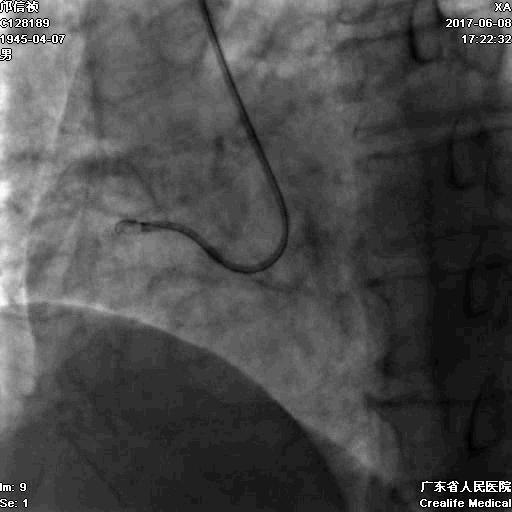

第二步:处理LCX

Fielder XT-A,Gaia First ---在微导管支撑下通过闭塞病变

LCX植入支架

2.0*10mm球囊

2.75*22mm药物支架